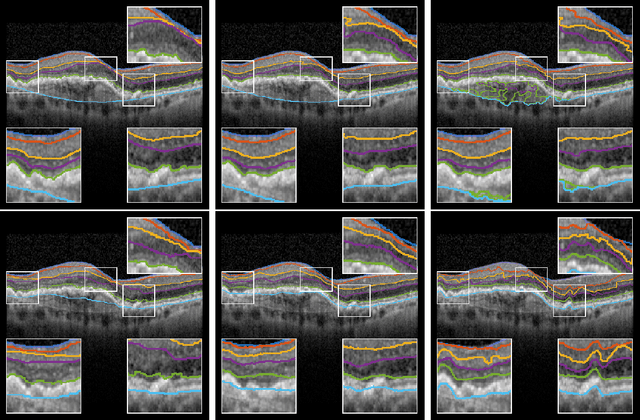

The automatic segmentation of retinal layer structures enables clinically-relevant quantification and monitoring of eye disorders over time in OCT imaging. Eyes with late-stage diseases are particularly challenging to segment, as their shape is highly warped due to pathological biomarkers. In this context, we propose a novel fully Convolutional Neural Network (CNN) architecture which combines dilated residual blocks in an asymmetric U-shape configuration, and can segment multiple layers of highly pathological eyes in one shot. We validate our approach on a dataset of late-stage AMD patients and demonstrate lower computational costs and higher performance compared to other state-of-the-art methods.